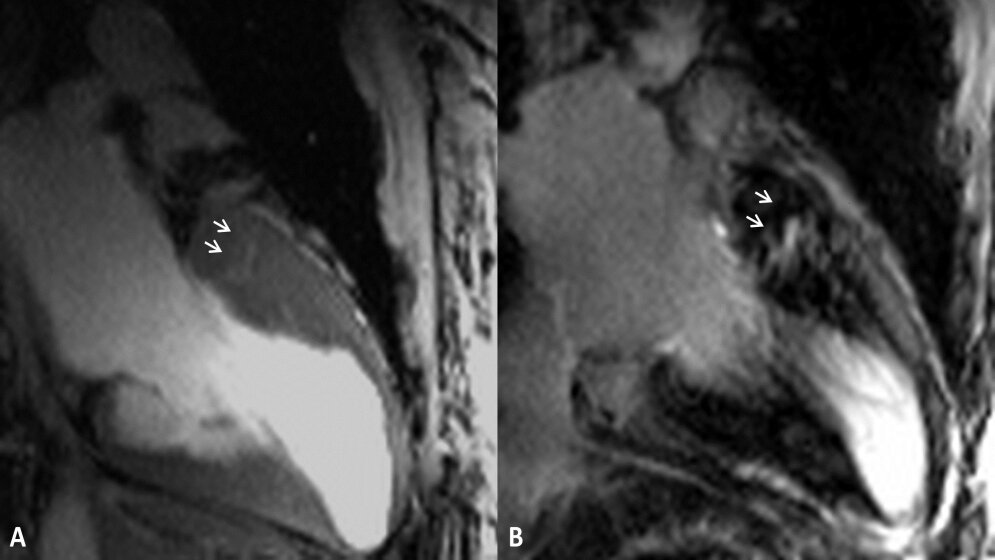

Veränderungen oder Schäden des Herzmuskels lassen sich so besser erkennen und bewerten, beispielsweise bei Patienten mit einer genetisch bedingten Verdickung der linken Herzkammer, einer Hypertrophen Kardiomyopathie (HCM). Aufgrund der Gewebedifferenzierung im Herzmuskelbereich werden am leistungsstarken 7-Tesla-Scanner Mikrostrukturen sichtbar, darunter krankhafte Veränderungen oder Vertiefungen in der Muskulatur.

Den Forschern ist es gelungen, winzige Vertiefungen im Muskelgewebe, sogenannte myokardiale Krypten, nachzuweisen, die am klinischen Gerät dort nicht erkennbar waren. Ermöglicht wurde dies durch eine enge Kooperation mit der Berlin Ultrahigh Field Facility (B.U.F.F.) am Max-Delbrück Centrum für Molekulare Medizin (MDC) unter der Leitung von Prof. Dr. Thoralf Niendorf. Gemeinsam haben die Wissenschaftler Patienten mit verdickter Herzmuskulatur am 7-Tesla-Gerät mit 2D CINE-Bildgebung wie auch am herkömmlichen 3-Tesla-Gerät gescannt und die Aufnahmen des Herzens verglichen. Zusätzlich sind gesunde Vergleichspersonen mithilfe der neuen Geräte-Generation untersucht worden.

Nach Auswertung aller Daten kommen die Wissenschaftler zu dem Schluss, dass eine Untersuchung am 7-Tesla-MRT bei Patienten mit Hypertropher Kardiomyopathie sinnvoll sein kann. „Bei sieben von dreizehn Patienten konnten wir kleinste Vertiefungen im Muskelgewebe der linken Herzkammer gut sichtbar nachweisen“, sagt Dr. Marcel Prothmann, Erstautor der Studie. „Das räumlich hochauflösende Verfahren ist ein Qualitätssprung in der Bildgebung. Es ermöglicht eine detaillierte Visualisierung struktureller Veränderungen innerhalb von Abschnitten ausgedehnter Herzmuskelverdickung“, so der Mediziner. Die präzisen Abbildungen können dazu beitragen, genauere Aussagen über die Ursachen einer Herzinsuffizienz oder anderer Erkrankungen des Herzens zu treffen. (idw, red)